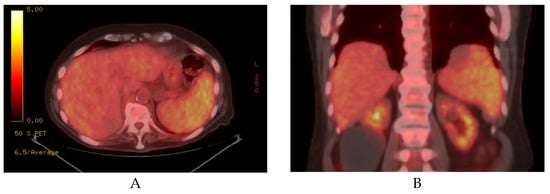

7. Clinical Vignette